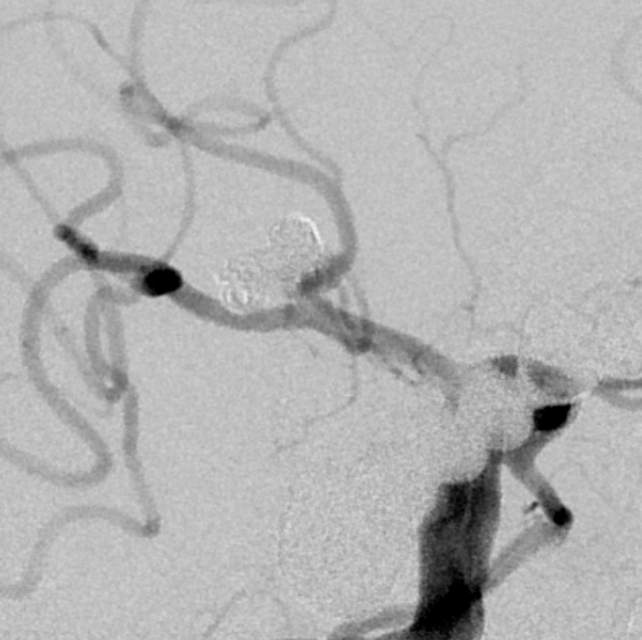

我们在工作中,有时也会遇到比较棘手的问题。譬如下面这个破裂的分叶状的宽颈动脉瘤,两个不大不小不能忽视的子囊还拥有一个共同的大本营—绝对宽颈的瘤体,动脉瘤也通过“犄角之势”成为一个硬骨头,想要拿下它绝非易事。单独出兵(栓塞)容易孤兵深入,首尾难顾,甚至可能需要采用挽救性技术来搬救兵保护粮道(载瘤动脉),万一失利,劳师伤财;使用1-2个支架辅助手术呢,由于急性期抗血小板不足术中可能出现急性血栓堵塞粮道,万一瘤体又不能致密栓塞一网打尽,术后抗血小板吧,怕出血;不抗血小板吧,又担心血栓。一旦遭遇此种境遇,战争(手术)的走向和主动权就无法掌握在指挥者(术者)手中,只能听天由命了……

话归正传,下面我们看看如何分兵使用“犄角之势”的策略夹击栓塞“犄角之势”的硬骨头(分叉部绝对宽颈带有俩角的动脉瘤):两个微导管先后到位,两个子囊内的弹簧圈相互依偎,形成“犄角之势”,共同击杀两者之间的大本营(共同的瘤体),最终致密栓塞动脉瘤,消除了动脉瘤再次兴风作浪(再出血)的风险,也最大限度的保全了各个分支血管(粮道)的安全,急性期也没有使用支架,降低了费用,还保障了安全。